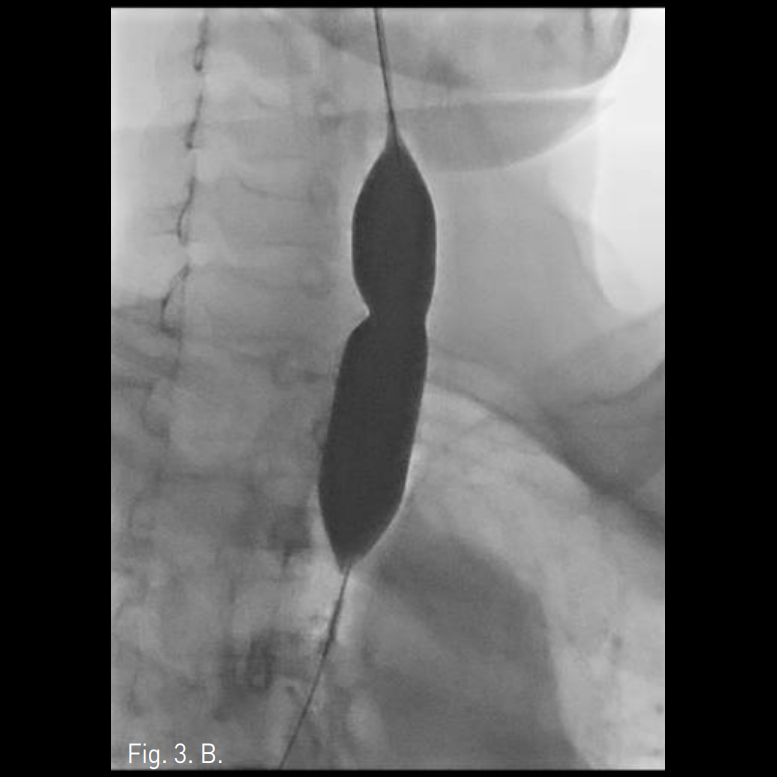

Supine position에서 국소마취 후 bronchoscopic guidance하에 0.035 inch stiff guide wire를 segmental bronchus level 이하까지 전진 시킨 후 5F sizing catheter를 삽입 후 병변의 위치 및 정도를 bronchography를 통하여 확인함. 병변을 확인한 후 15mm 및 20mm x 60mm balloon catheter를 통하여 dilatation을 시행함(Fig. 3). 시술 직후 bronchoscopy에서 web이 찢어지고 내경이 상당히 넓어져 있음(Fig. 4). 한달 후의 투시영상에서 잘 넓어져 있는 상태가 유지됨(Fig. 5).

Fig. 3

A-C. Successful luminal dilatation was done using 15mm and 20mm balloon catheters.